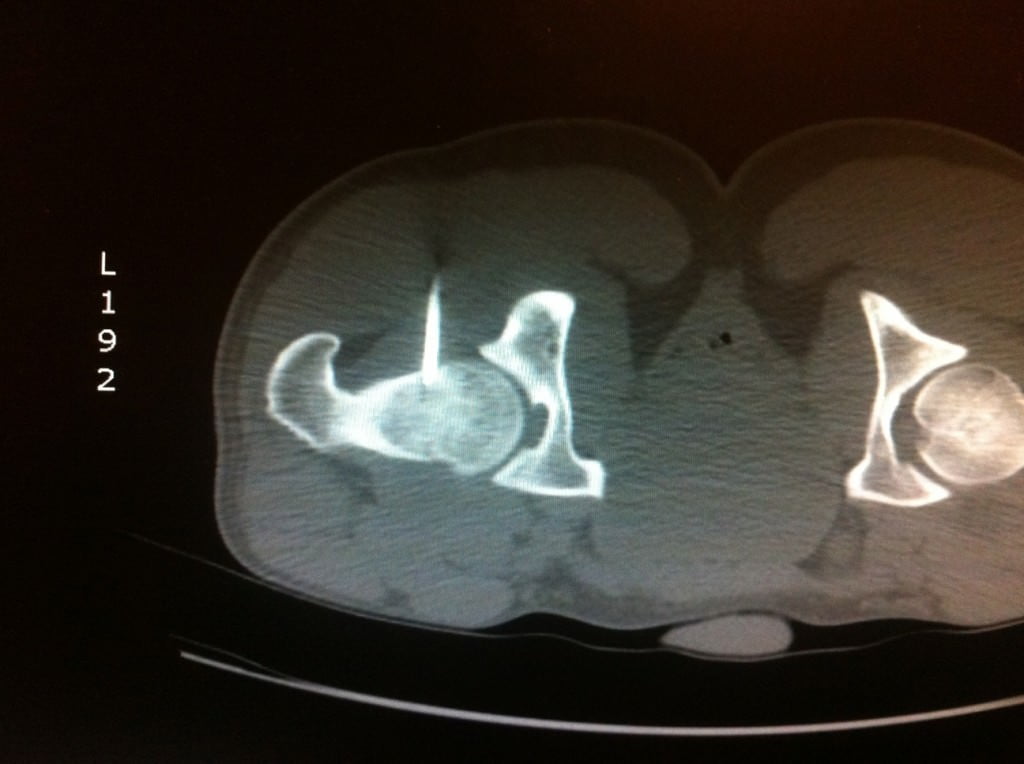

L’Examen est centré sur la région d’intérêt par Acquisition hélicoïdale de Coupes de 1 à 2mm jointives

Le scanner permet de repérer :

Le Nidus = hypodensité à contours nets associé à une hyperdensité calcique linéaire centro-tumorale correspondant à la vascularisation centrale. Une zone hypodense osseuse linéaire au niveau perilésionnel en regard de la condensation est assez spécifique. L’Ostéocondensation périphérique est homogène et peut provoquer une réaction périoste.